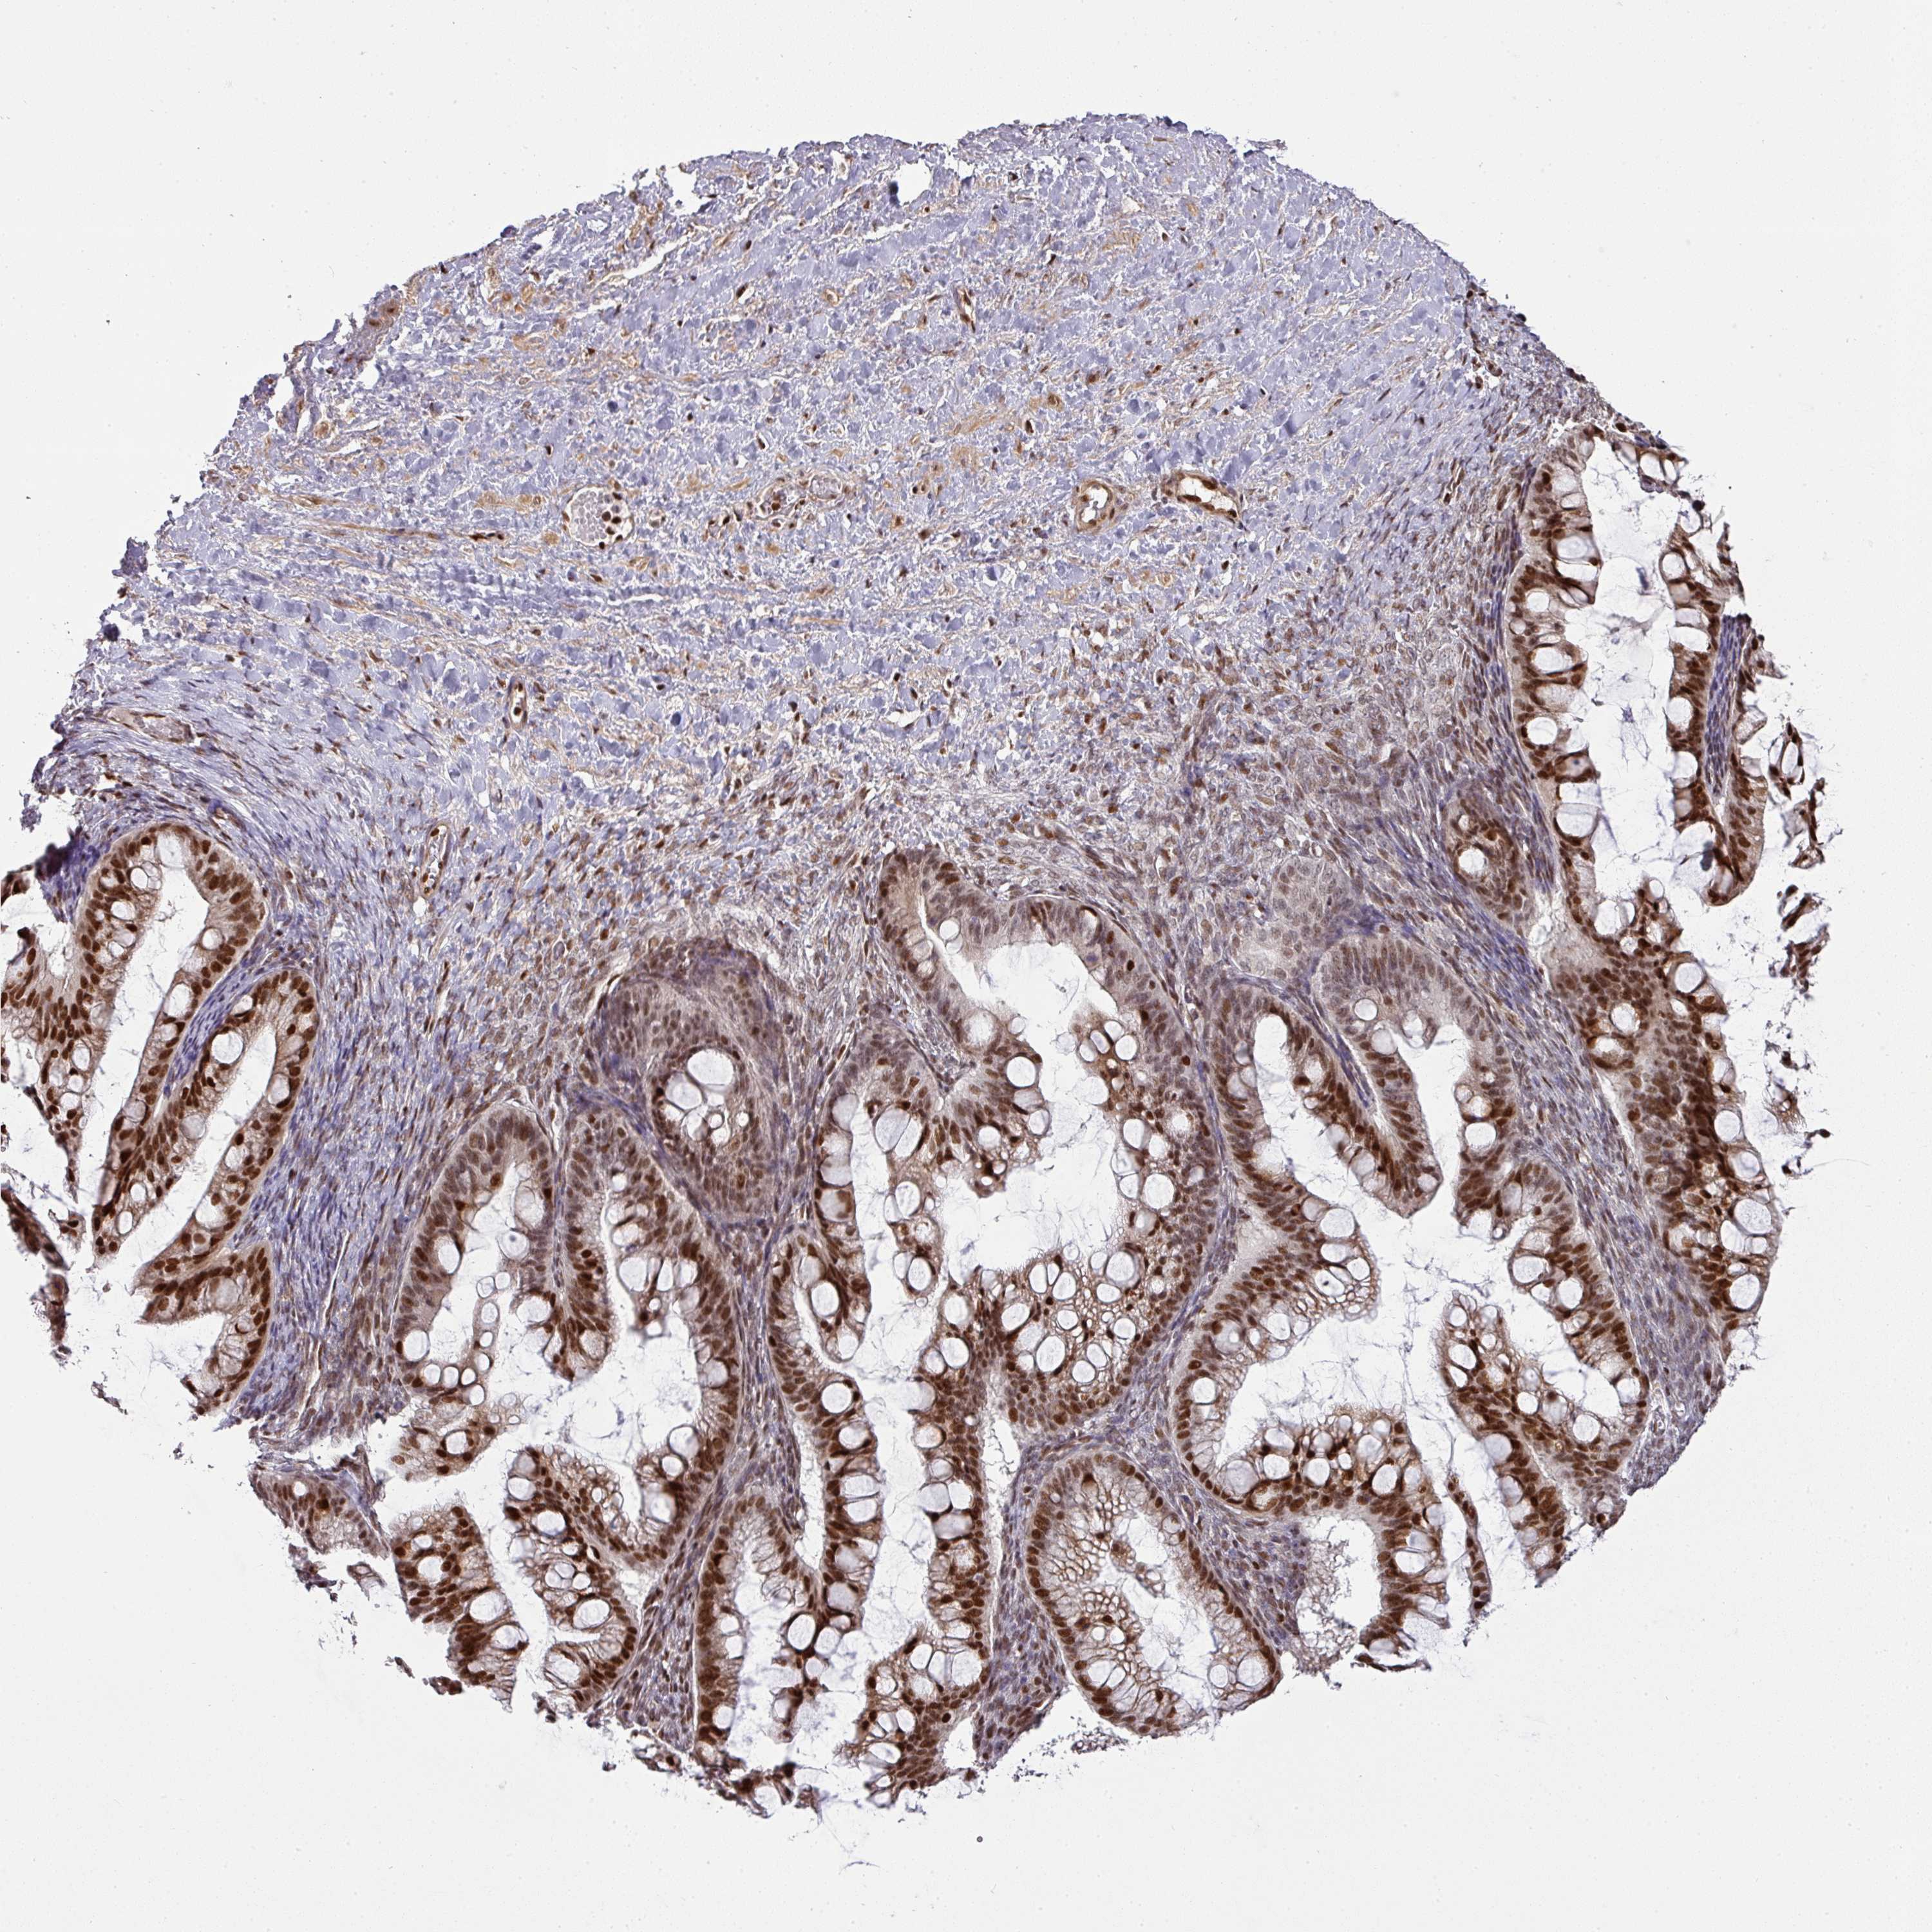

OVARIAN CANCER - Protein expressioni

A mouse-over function shows sample information and annotation data. Click on an image to view it in a full screen mode. Samples can be filtered based on level of antibody staining by selecting one or several of the following categories: high, medium, low and not detected. The assay and annotation is described here.

Note that samples used for immunohistochemistry by the Human Protein Atlas do not correspond to samples in the TCGA dataset.

Antibody stainingi

Antibody staining in the annotated cell types in the current human tissue is reported as not detected, low, medium, or high, based on conventional immunohistochemistry profiling in selected tissues. This score is based on the combination of the staining intensity and fraction of stained cells.

Each image is clickable and will lead to virtual microscopy that enables deeper exploration of all samples and also displays staining intensity scores, fraction scores and subcellular localization as well as patient and tissue information for each sample.

Antibody HPA054291

Staining

High

Medium

Low

Not detected

Intensity

Strong

Moderate

Weak

Negative

Quantity

>75%

75%-25%

<25%

None

Location

Nuclear

Cytoplasmic/membranous

Cytoplasmic/membranous,nuclear

Cystadenocarcinoma, serous, NOS

Carcinoma, NOS

Cystadenocarcinoma, mucinous, NOS

Carcinoma, endometroid